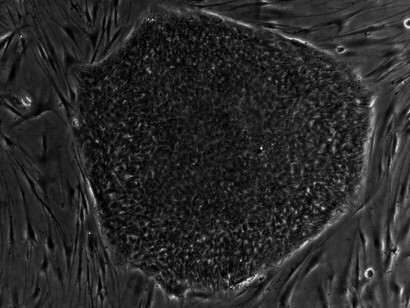

Mesenchymal stem cells (MSCs) are stromal cells that can differentiate into many lineages and self-renew. Numerous tissues, including the umbilical cord, endometrial polyps, menstrual blood, bone marrow, adipose tissue, etc., can yield MSCs.

Cells from bone marrow or adipose tissue are harvested, processed, and then reintroduced into the injured area. This strategy allows your body to repair naturally, resulting in less pain and a speedier recovery.

Autologous chondrocyte implantation (ACI) and matrix-assisted chondrocyte implantation (MACI) are two methods used in stem cell therapy for the repair of osteochondral defects by employing chondrocyte transplantation. Over a ten-year period, both procedures have demonstrated successful outcomes in treating osteochondral defects of the knee in 70–80% of patients. The process has virtually no side effects and is the only method known to produce satisfactory results with graft survival of at least ten years.